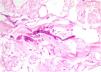

Despite adequate treatment, this infection has high mortality (40%–63%), and its prevalence has increased, probably due to the growing number and higher survival rates of immunosuppressed patients4,5. Most infections are life threatening, as the fungus has particular affinity for vascular walls that cause irreversible damage through thrombosis and ischemic necrosis. Figures 1 and 2 present biopsy specimens taken from patients for diagnosis, and the fungus can be seen invading the normal tissue.